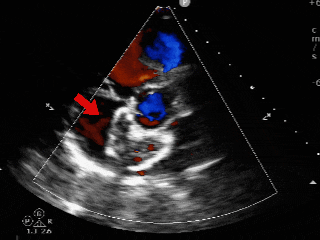

CDFI:房水平可见一股红色彩流由左房经缺口进入右房。主动脉瓣下左室流出道探及微量舒张期反流信号。三尖瓣口右房侧探及微量收缩期反流信号,Vp 2.7m/s,PG 29mmHg。二尖瓣口左房侧探及微量收缩期反流信号。

超声可见房间隔连续中断,彩色多普勒可见过隔血流

测量房间隔缺损直径最大为23.9mm,房间隔总长53.8mm

心尖四腔心切面可见封堵器形态良好

主动脉短轴切面可见封堵器呈“Y”字型抱住主动脉

彩色多普勒血流成像显示无残余分流存在